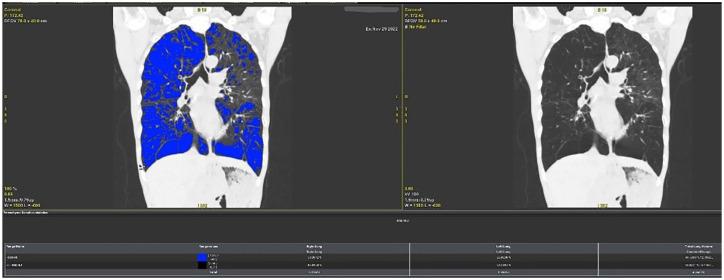

Objective: This study aimed to evaluate the characteristics of emphysema in patients with COPD using quantitative computed tomography (QCT) and to investigate the relationship between the extent of emphysema, clinical phenotypes, lung function, and plasma concentrations of VEGF and IL-1β in COPD patients.

Methods: The emphysema index (EI) was quantified using QCT of the chest and categorized into levels from 0 to 4. Data on acute exacerbation frequency, CAT scores, mMRC, pulmonary function indices, arterial blood gas measurements, and plasma concentrations of VEGF and IL-1β were collected and analyzed to determine their relationship with EI.

Abstract Image